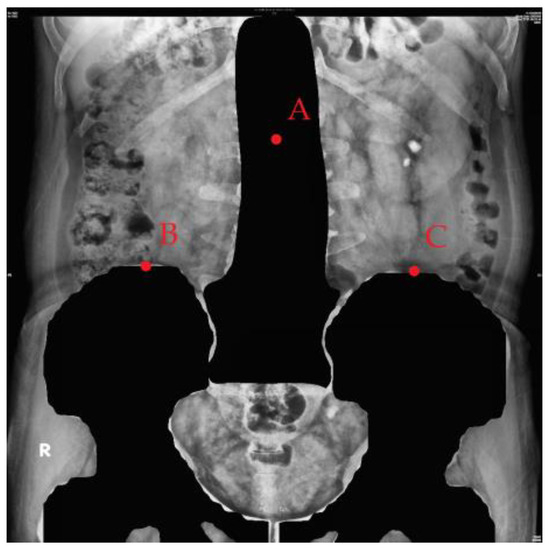

2.3.3. Image Cropping